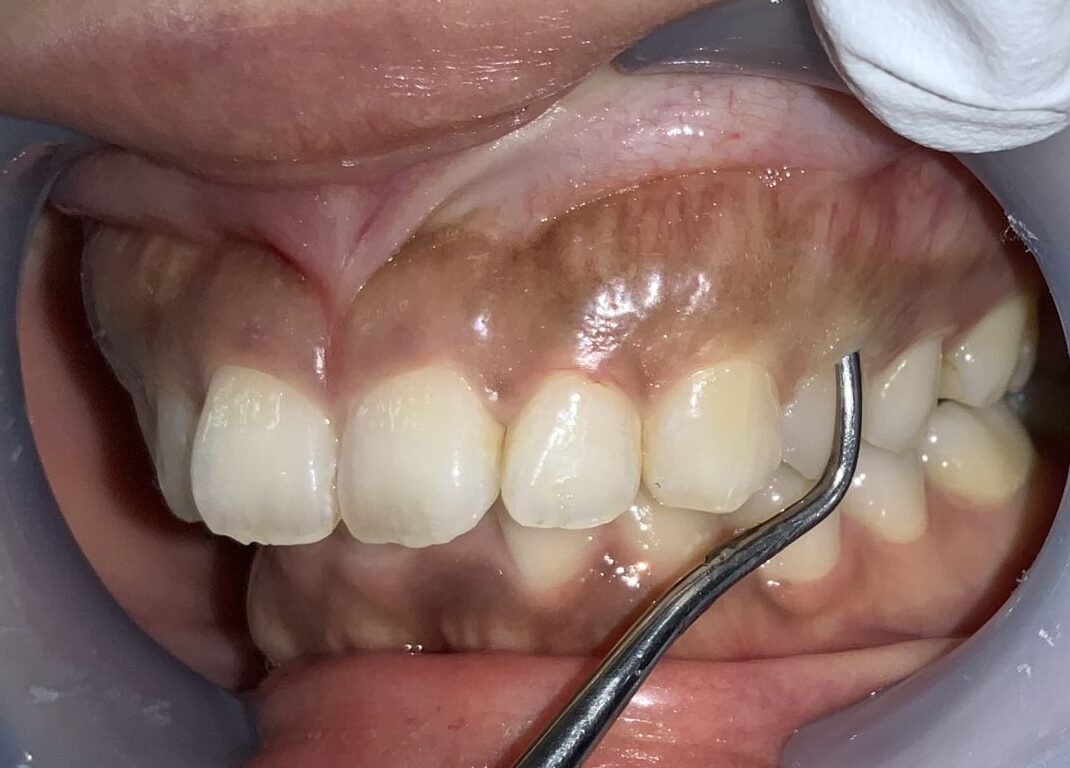

まずは手術前の状態です。

歯に歯ぐきがたくさんかぶっている状態です。

まずは歯ぐきのかぶり具合、歯ぐきの厚み、歯槽骨の状態、歯ぐきの切除範囲の検査からです。

このくらいかぶっていますから、綺麗に切除できます。